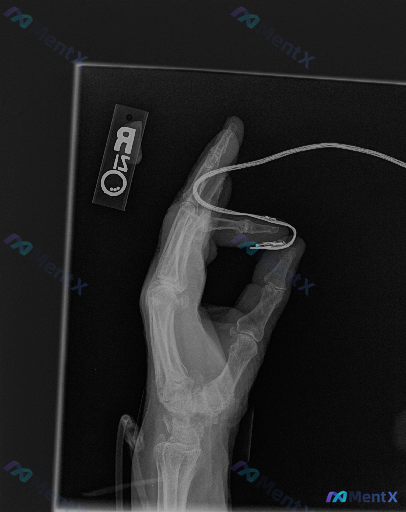

整理到一张右手部X光正位的影像资料,先和大家同步客观发现: 1. 腕关节舟骨区域可见金属内固定物(微型螺钉)影,提示既往舟骨骨折切开复位内固定术后改变;骨折线部分模糊,未见明确新鲜骨折线; 2. 其余掌骨、指骨骨皮质连续,骨小梁结构基本清晰;各腕关节、掌指关节、指间关节间隙基本正常,对位良好,关节面...